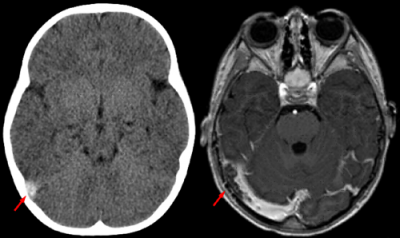

I risultati ottenuti con la Risonanza Magnetica, sono di gran lunga più esaurienti e dettagliati delle immagini offerte dalle tradizionali radiografie, la differenza tra le due è notevole, nella RMN il segnale di densità è dato dal nucleo atomico della parte esaminata, mentre in radiologia, la densità è determinata dagli orbitali elettronici degli atomi, che vengono interessati dai raggi X.

Questo esame fa pur sempre parte della radiologia, in quanto genera immagini relative alla struttura interna del corpo umano, ma fornisce elementi di natura diversa, infatti l'RMN, mette in evidenza solo i tessuti molli, facendo una netta distinzione tra le diverse tipologie, dando un risultato finale, difficilmente ottenibile con le altre forme di radiologia. Essa è in grado di produrre immagini di tipo tomografico digitale, utilizzando campi magnetici e radiofrequenze, si può definire una tecnica multiparametrica e multiplanare, che permette di ottenere sezioni di organi e vario orientamento su piani sagittali, dorsali o trasversali, con assenza di artefatti, dovuti alle strutture ossee e soprattutto senza alcun bisogno di spostare il paziente.

- Patologie oncologiche a livello cerebrale e nella ricerca delle funzioni ad esso collegate,